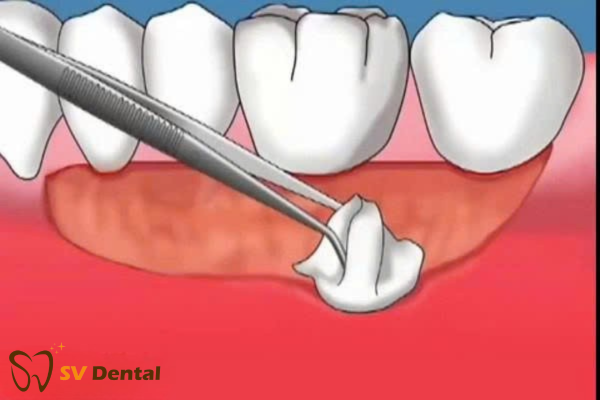

2. Điều trị phẫu thuật – ghép lợi

• Ghép lợi tự do (tự thân)

Dùng mô ở hàm ếch để phủ chân răng.

• Ghép mô liên kết dưới biểu mô

Hiệu quả cao, phù hợp nhiều trường hợp tụt lợi phức tạp.

• Tái tạo mô có hướng dẫn bằng màng sinh học

Chi phí cao nhưng phục hồi mô nha chu rất tốt.